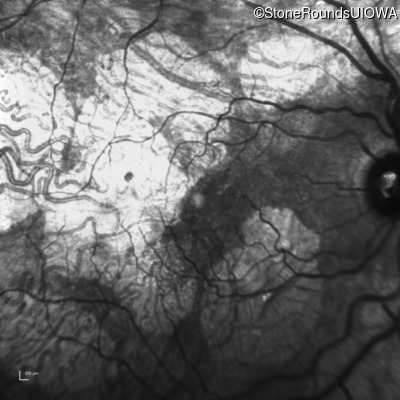

Age at visit: 51 years

OD OS

This 51 year old woman first experienced some abnormality in her distance vision when she was 27 years old. She feels that her vision has been stable since that time.